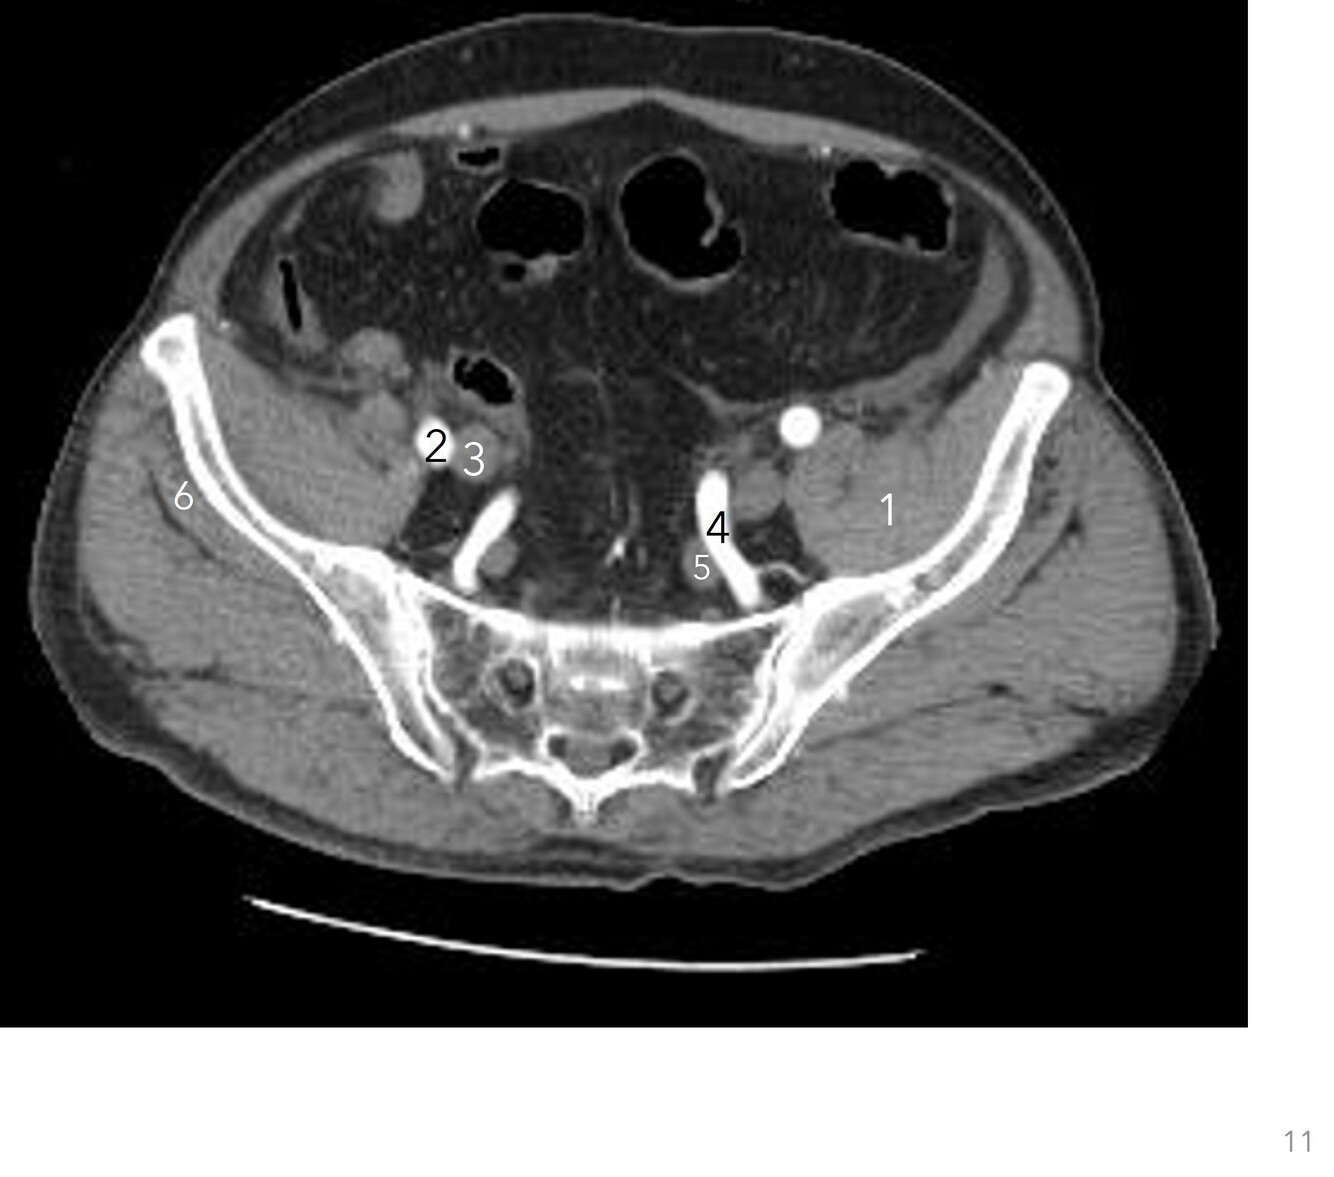

11

Q

Label 1-6

A

1. Lt iliopsoas

2. Rt external iliac artery

3. Rt external iliac vein

4. Lt internal iliac artery

5. Lt internal iliac vein

6. Rt gluteus minimus

How well did you know this?